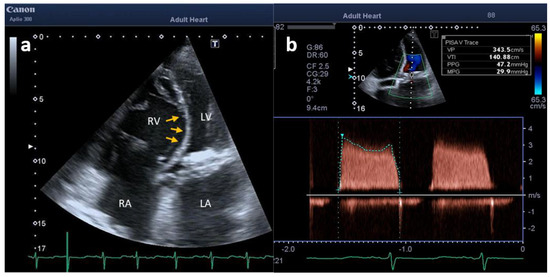

2. Case Description